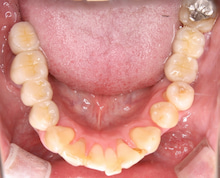

下の写真は 2年後の定期検診時の写真です。

結局 3本のインプラントを行い、

銀歯は ハイブリッドセラミック

と呼ばれるかぶせものに替えました。

歯周病は治癒しました。